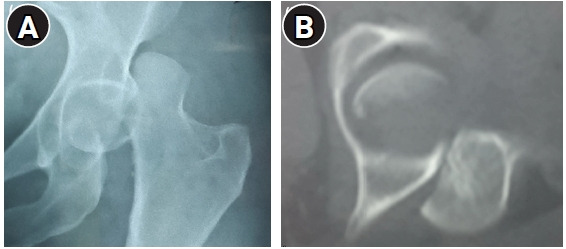

Femoral head fractures with associated hip dislocations substantially impact the functional prognosis of the hip joint and present a surgical challenge. The surgeon must select a safe approach that enables osteosynthesis of the fracture while also preserving the vascularization of the femoral head. The optimal surgical approach for these injuries remains a topic of debate. A 44-year-old woman was involved in a road traffic accident, which resulted in a posterior iliac dislocation of the hip associated with a Pipkin type II fracture of the femoral head. Given the size of the detached fragment and the risk of incarceration preventing reduction, we opted against attempting external orthopedic reduction maneuvers. Instead, we chose to perform open reduction and internal fixation using the Watson-Jones anterolateral approach. This involved navigating between the retracted tensor fascia lata muscle, positioned medially, and the gluteus medius and minimus muscles, situated laterally. During radiological and clinical follow-up visits extending to postoperative month 15, the patient showed no signs of avascular necrosis of the femoral head, progression toward coxarthrosis, or heterotopic ossification. The Watson-Jones anterolateral approach is a straightforward intermuscular and internervous surgical procedure. This method provides excellent exposure of the femoral head, preserves its primary vascularization, allows for anterior dislocation, and facilitates the anatomical reduction and fixation of the fracture.